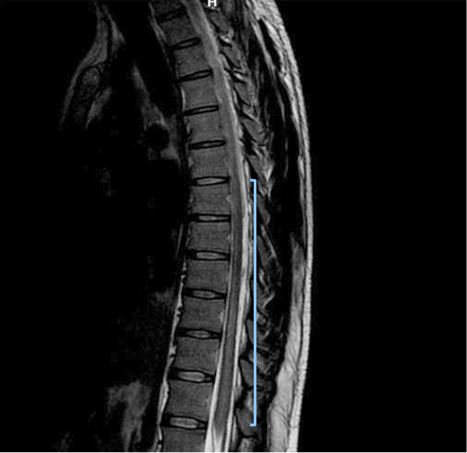

Due to early vesical incontinence, magnetic resonance imaging of the thoracolumbar spine was performed, which showed an alteration in the intensity of the spinal cord observed from the T2 level to the conus medullaris, which initiates in the anterior horns and then generalizes throughout the circumference of the spinal cord with significant thickening. These findings were consistent with longitudinally extensive transverse inflammatory myelopathy (Figure 1, 2, and 3).

Figure 3. Sequence T2